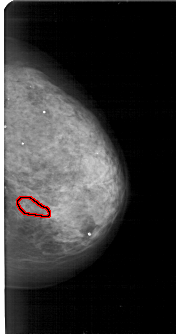

A_1810_1.LEFT_CC

LEFT_CC LINES 5491 PIXELS_PER_LINE 2971 BITS_PER_PIXEL 12 RESOLUTION 43.5 NON_OVERLAY

FILE: A_1810_1.RIGHT_CC.OVERLAY

TOTAL_ABNORMALITIES 1

ABNORMALITY 1

LESION_TYPE CALCIFICATION TYPE PLEOMORPHIC DISTRIBUTION CLUSTERED

ASSESSMENT 4

SUBTLETY 2

PATHOLOGY BENIGN

TOTAL_OUTLINES 1

BOUNDARY